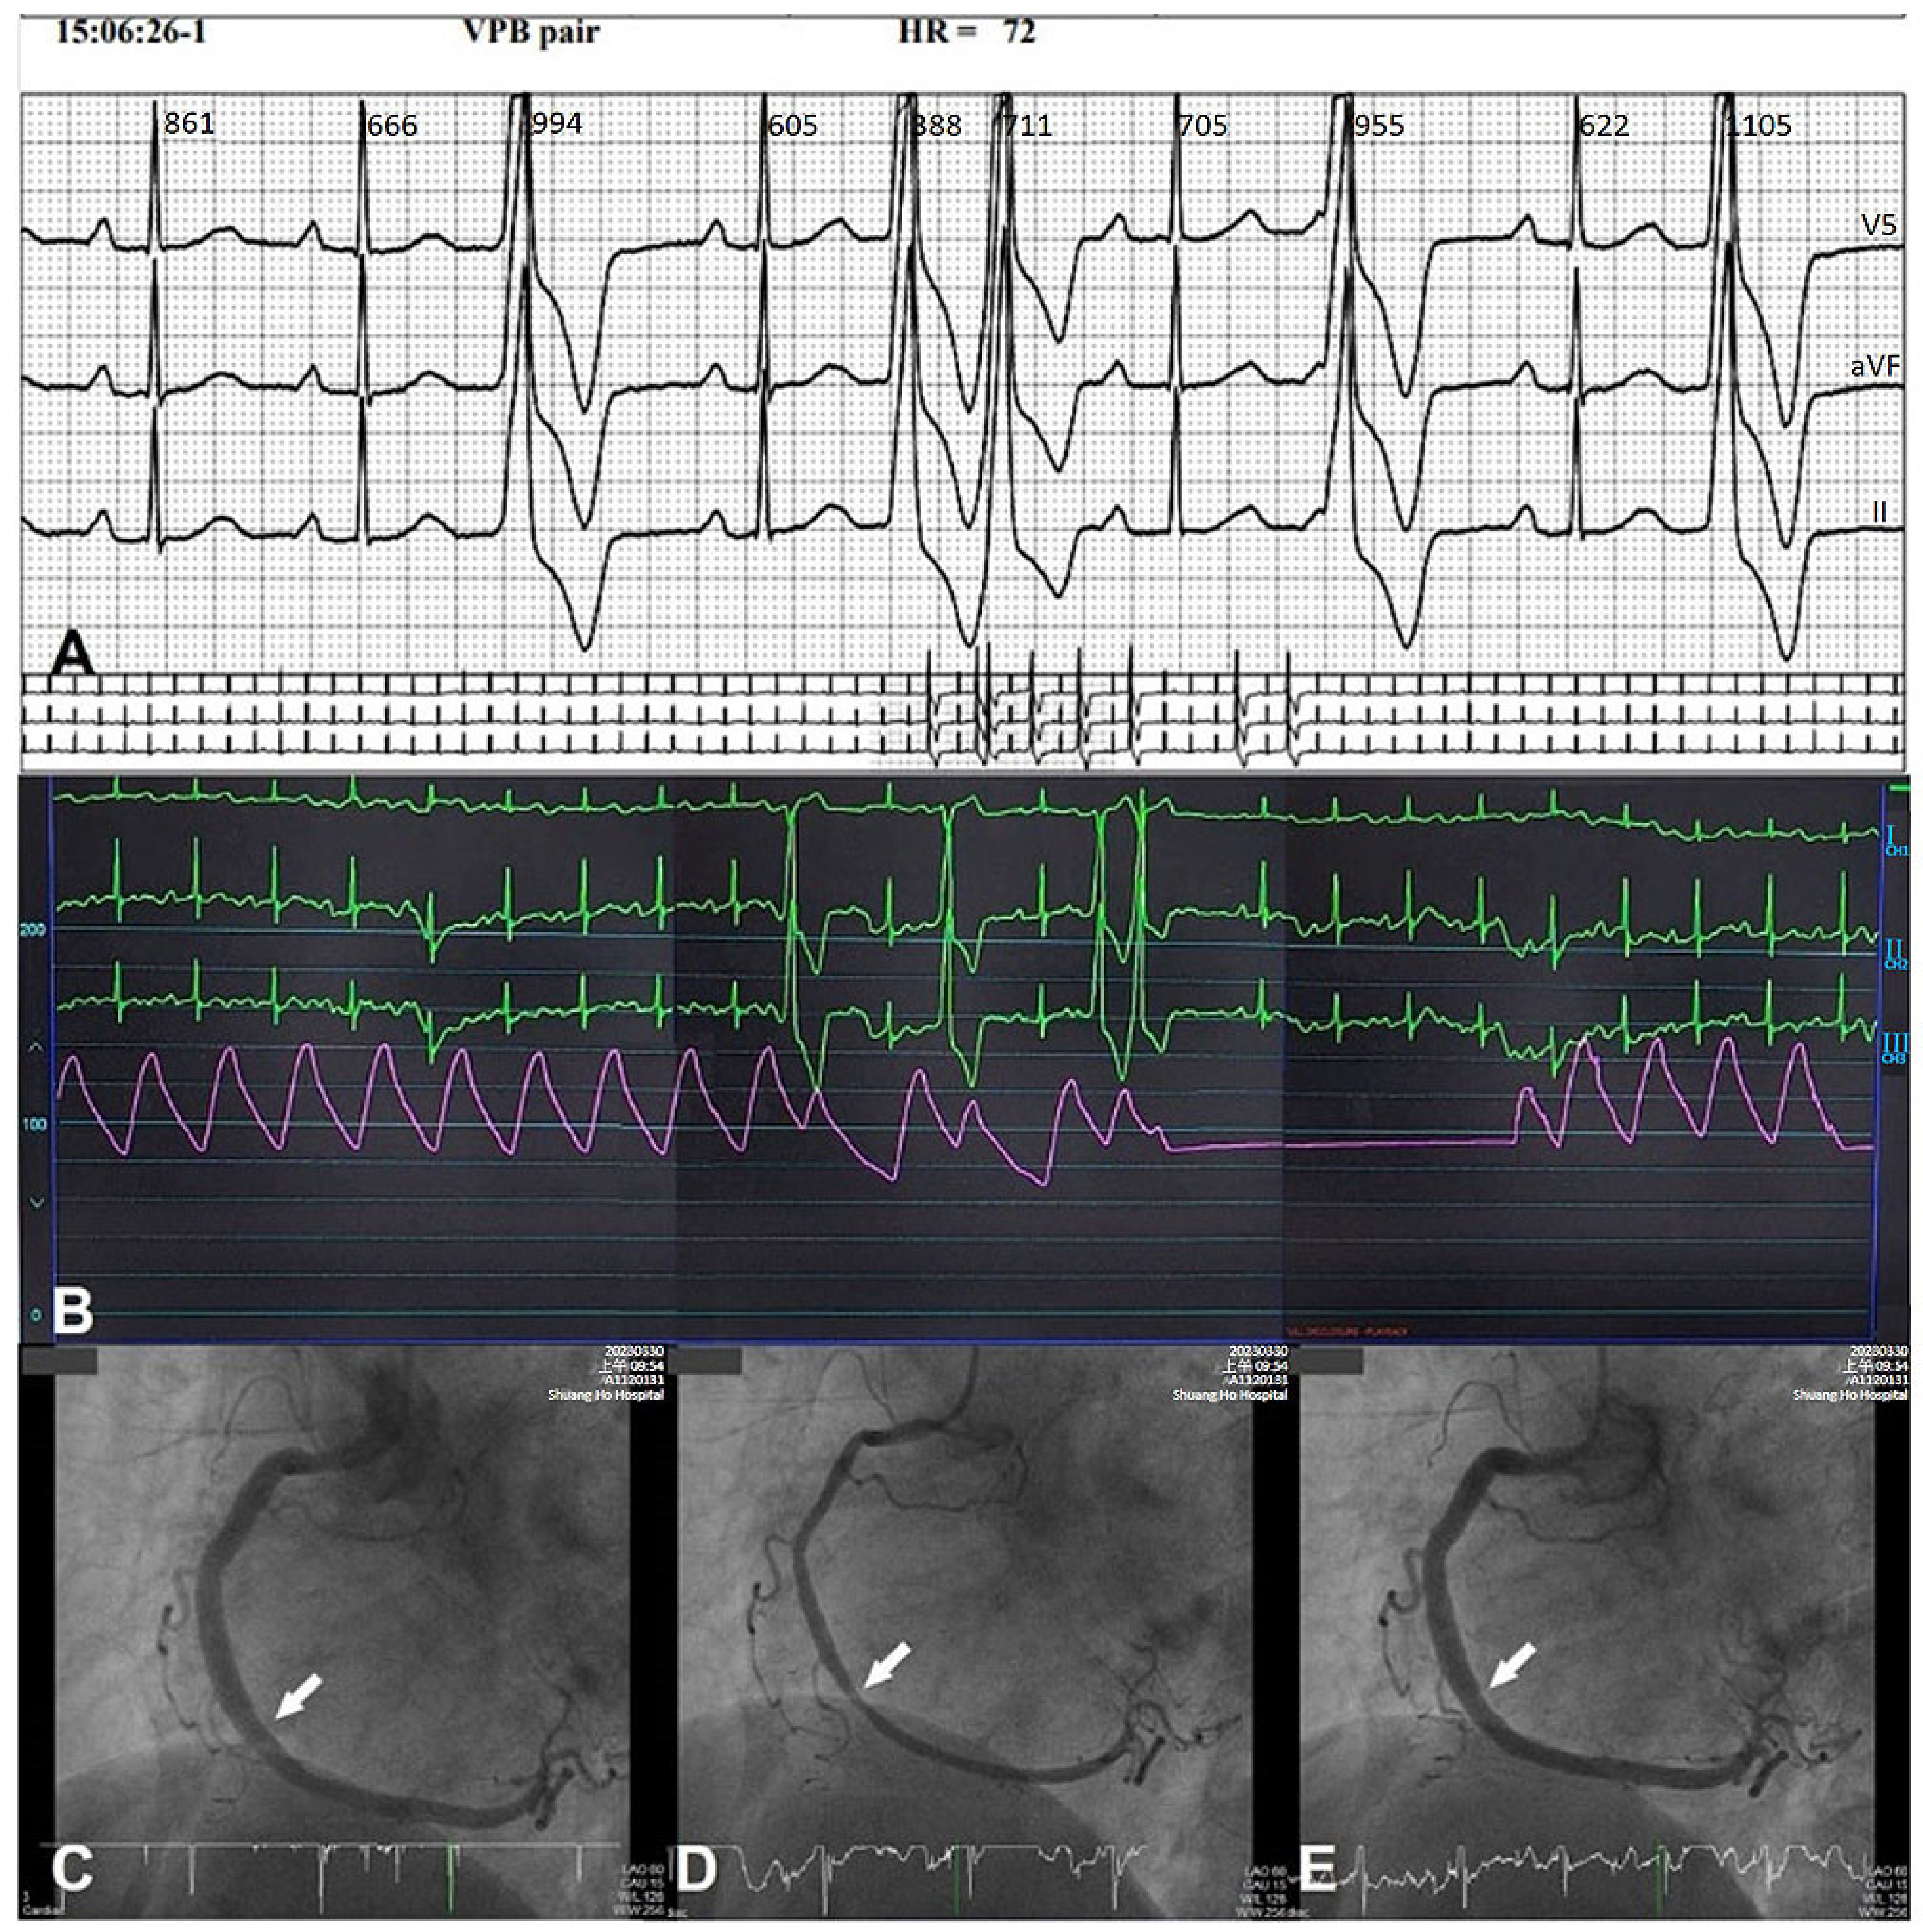

3. Clinical Features of CASHF

4.2. Epicardial CASHF